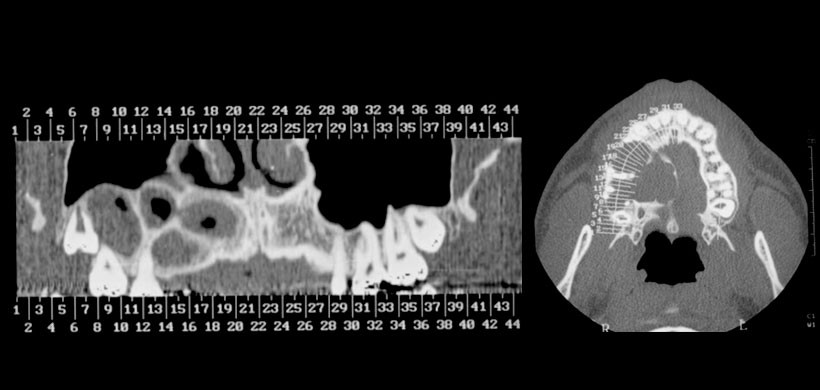

Radiográficamente, el 52% de las lesiones eran uniloculares y el 48% eran multiloculares; el 94,5% mostró bordes bien definidos. La información sobre la integridad de la cortical estaba disponible en sólo 24 casos: 50% mostró una perforación, un 8,3% erosión de las corticales y 8,3% adelgazamiento de estas mismas. (Fig 2) En cuanto a la reabsorción radicular se encontró en un 22% y en un 24% el desplazamiento de los dientes.(Fig 3)

Mediante este estudio se pudo llegar a la conclusión que el quiste odontogénico glandular (quiste sialodontogenico) tiene un comportamiento potencialmente agresivo, con la expansión y la perforación de las corticales.

También se menciona que es recomendable el uso de la tomografía volumétrica de haz cónico para este tipo de lesión especialmente las de gran tamaño, y más aún si son multiloculares o implican algún tipo de alteración respecto a dientes y/o estructuras adyacentes.